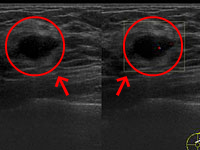

乳腺エコーは、乳房に超音波を当てることで、リアルタイムに腫瘤(しゅりゅう)などの病変を検出する検査です。がん組織がある場合、その形が黒く浮かびあがります。乳腺の影響を受けにくく診断できるため、一般に乳腺組織が発達している40歳以下の方には特に有効な検査です。その一方で、乳腺の微細な石灰化を描画するのはマンモグラフィーと比較すると不得意とされています。